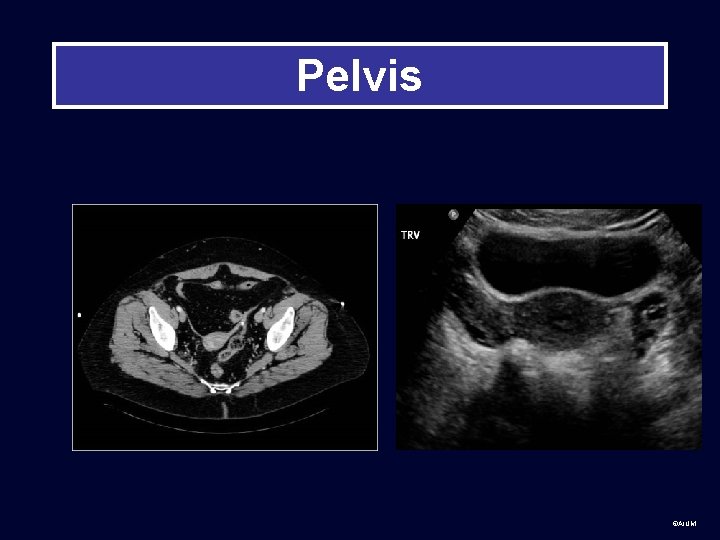

Pelvis ©AIUM

Anatomy Pelvis R ovary L ovary Bladder Vagina Uterus: cervix, body, fundus ©AIUM